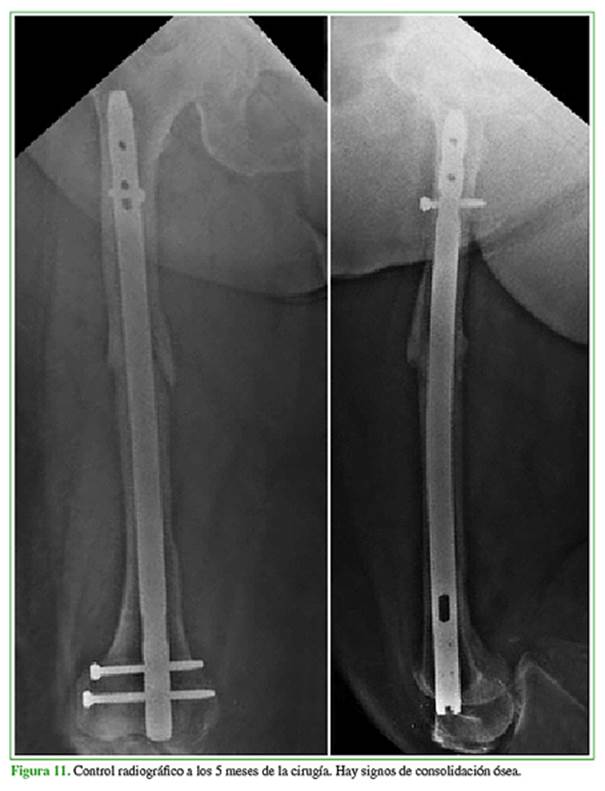

Se procedió al fresado creciente y a la colocación del clavo endomedular retrógrado de 14 mm x 340 mm, sin complicaciones.

En los siguientes controles radiográficos, se confirmó la consolidación a los cinco meses (Figura 11).